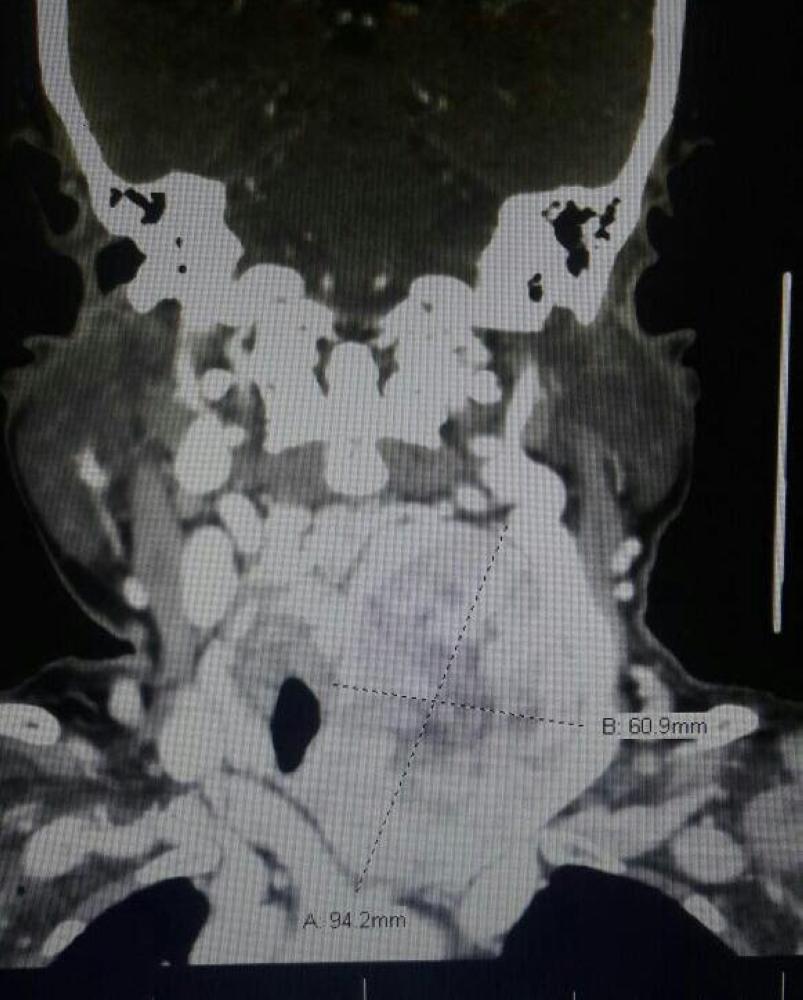

نجح فريق طبي من قسم الجراحة العامة بمستشفى الملك خالد بنجران بإنهاء معاناة سيدة تبلغ من العمر 82 عاما من ورمِ كبير غير حميد في الرقبة ممتد إلى تجويف الصدر، أدى إلى ازاحة القصبة الهوائية إلى الجهة اليمنى، مما أدى الى صعوبة في التنفس والشعور بالاختناق مع تغير في الصوت وصعوبة في البلع.

وأوضحت "الصحة" أنه بعد استكمال الاجراءات الطبية لمثل تلك الحالات ومعاينتها من قبل جميع التخصصات المعنية، ومناقشة الحالة من قبل الفريق الطبي المكون من الجراحة العامة وجراحة الصدر والأورام والتخدير والأشعة، لتحديد مدى امكانية اجراء التدخل الجراحي من عدمه، خاصة وأن المريضة كبيرة في العمر وتعاني من أمراض مزمنة، وتم الاتفاق على العمل الجراحي مع أخذ جميع الاحتياطات، واجريت العملية بكل نجاح ولله الحمد، وتم استئصال الورم كاملاً دون مضاعفات. وأبانت "الصحة" ان المريضة تلقت الرعاية الطبية في قسم التنويم لمدة أربعة أيام بعد العملية وغادرت المستشفى وهي بحالة صحية مستقرة.